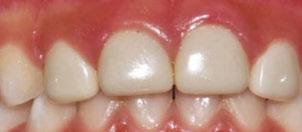

Several clinical solutions exist for primary anterior teeth with multisurface decay. Full coronal restoration of carious primary incisors may be indicated when caries is present on multiple surfaces, pulpal therapy is indicated, caries may be minor, but oral hygiene is very poor, or in a child with severe early childhood caries or a high caries risk diagnosis.1 Depending on the clinical scenario, a minimally invasive approach with the utilization of a high viscosity glass ionomer cement (HVGIC), with or without the combination of silver diamine fluoride (SDF) in a strip crown form, may pause the caries progression and provide an adequate clinical solution. Resin composite strip crowns have shown 80% retention rates and adequate parental satisfaction,1-4 although composite resin strip crowns have shown lower retention rates in teeth with decay involving three or more surfaces and particularly in children with a high caries risk4-6 (Figure 1). This could be from the continued high caries risk behaviors of the patient, as composite resin strip crowns in this population have shown to have increased inflamed marginal gingiva and gingival bleeding, increased plaque retention along the restoration, and loss of some restorative material.5,6

Alternatively, a resin-faced stainless steel crown provides a full coverage restoration with excellent retention.7 These crowns can serve as a full-coverage restoration with or without the resin facing, but the loss of resin facing can be a major esthetic concern for parents.7 Preformed pediatric zirconia crowns address many of the undesirable clinical outcomes of other restorative materials. Their biocompatibility, demonstration of excellent marginal gingival health, low plaque retention, high parental esthetic acceptance, and high survival probabilities make them an excellent clinical choice in the patient with severe early childhood caries.1,4,5,8-13

With parental interest increasing in esthetic treatment options for complex anterior caries, preformed pediatric zirconia crowns are becoming the treatment of choice for patients with a high caries risk or a severe early childhood caries diagnosis.14

2: NuSmile® Anterior Zirconia crowns at 2-year follow up. Note the high amount of plaque accumulations along the untreated cuspid and existing stainless-steel crowns

This review discusses three clinical cases in which NuSmile® ZR (NuSmile, Houston, Texas) anterior pediatric zirconia crowns were the correct clinical decision in varying clinical scenarios.

A 2-year-old male who received full mouth dental rehabilitation (FMDR) under general anesthesia presented for his 6-month recall at 2-year post FMDR. He had significant plaque accumulations with poor oral hygiene along his existing stainless-steel crowns (SSCs) and non-treated teeth. Additionally, the patient had gingival bleeding and gingival inflammation

around these clinical sites. His anterior zirconia crowns showed healthy gingival margins with little-to-no plaque accumulations. This positive clinical finding is from the highly polished nature and biocompatibility of pediatric zirconia crowns. These restoration features limit plaque accumulations on the restoration and along the marginal gingiva, providing a localized positive aspect directly related to the choice of restorative material (Figure 2).